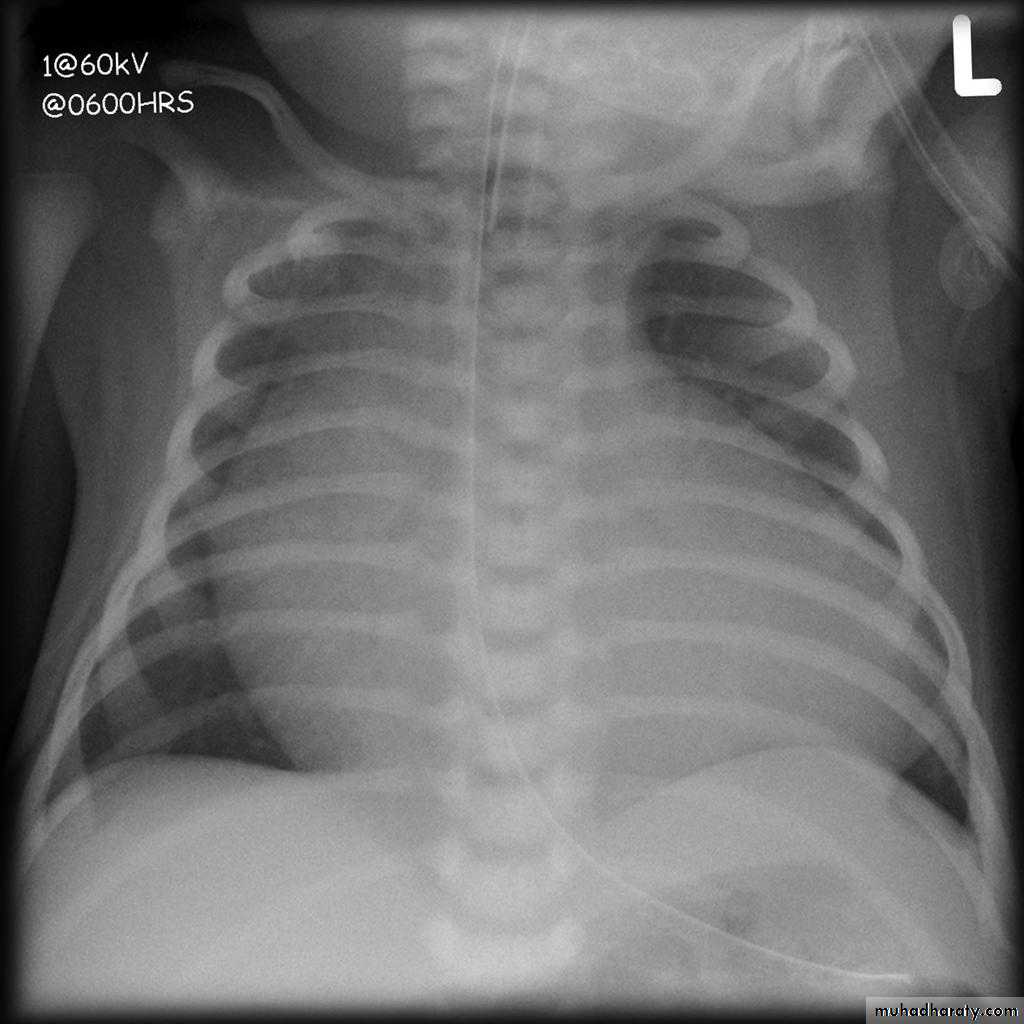

Tetralogy of Fallot (TOF) is one of the most common cyanotic congenital heart conditions and continues to be a major source of morbidity .

Tetralogy of Fallot is classically characterised by four features which are:

ventricular septal defect (VSD) 6

right ventricular outflow tract obstruction (RVOTO) due to:pulmonary artery stenosis

overriding aorta

right ventricular hypertrophy

Radiographic features

Plain film

Plain films may classically show :

1. "boot shaped" heart with an upturned cardiac apex due to right ventricular hypertrophy and concave pulmonary arterial segment.

2.Pulmonary oligaemia due to decreased pulmonary arterial flow.

3.Right sided aortic arch is seen in 25%.

"boot shaped" heart ( TOF )

TOF